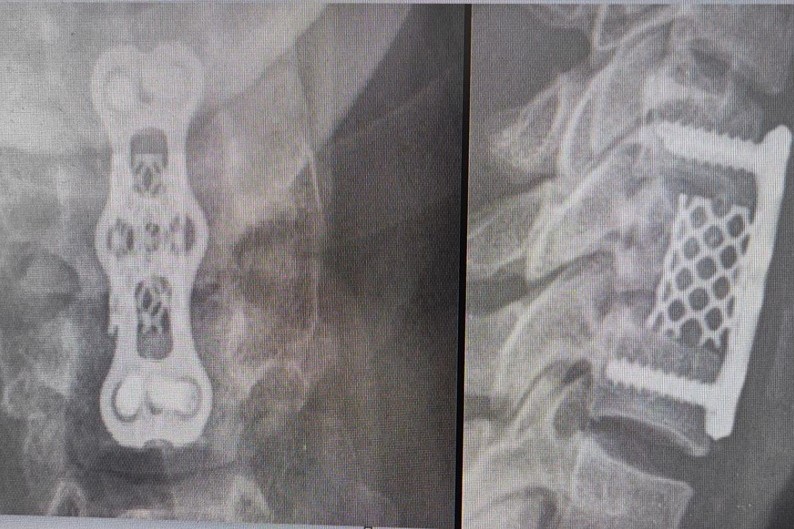

В каждом случаев пострадавшим потребовалось установить металлоконструкцию для стабилизации. Неделю пациенты провели в травматологическом отделении, после чего им назначили ношение специального корсета и отпустили долечиваться домой.

Ныряльщику с поврежденным первым шейным позвонком установили систему гало-фиксации. С этой конструкцией ему предстоит ходить до трех месяцев.